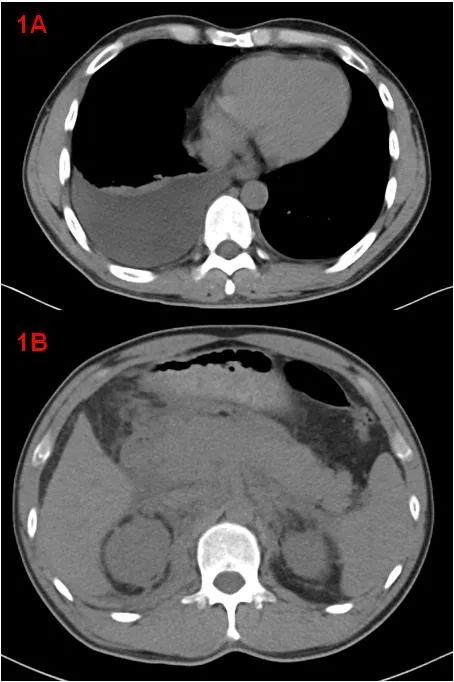

中年男性,體檢發現“雙腎積水”來診,余無明顯不適。CT示雙側胸腔積液、右肺膨脹不全(圖1A);胰腺腫大、胰周滲出,腹腔少量積液、腹膜、網膜增厚,腹膜后軟組織增厚(圖1B);考慮自身免疫性胰腺炎?腹膜后纖維化?

增強CT示腹膜后局部腹主動脈及其分支近端周圍餅狀軟組織腫塊(圖2),考慮腹膜后纖維化。建議完善IgG4相關檢查。